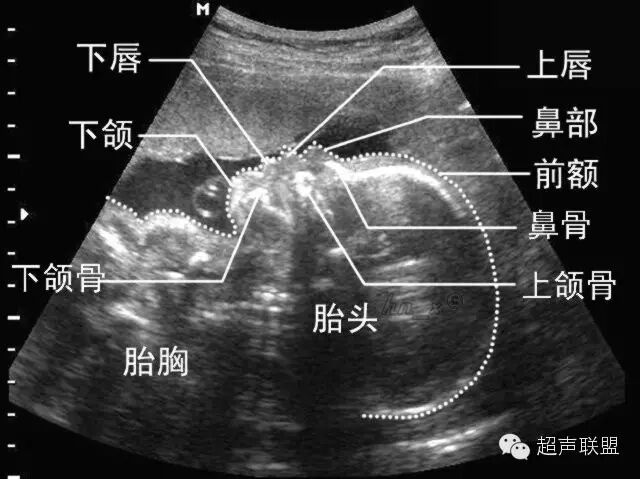

(三)正中矢状切面

1.扫查方法:胎儿仰卧位,探头置于胎儿面部正前方,声束平面通过胎儿鼻尖和额部作正矢状切面扫查,即可获此切面。

2.判断标准:下颌骨仅为圆点状高回声,鼻尖显示的同时只显示鼻柱,而不能显示鼻孔,同时显示额部而非眼眶回声。

3.主要观察的解剖结构及内容:前额、 鼻根、 鼻尖、 鼻柱、 上唇、 下唇、下颌及其深部的骨性结构如额骨、 鼻骨、上颌骨牙槽突、 下颌骨牙槽突,还可观察到口腔及舌,下巴则表现为有一定曲度的“S” 形。声束平面略向左或右平行移动,可显示出鼻孔、 眼球等结构。

4.临床意义:该切面是观察胎儿面部轮廓的良好切面,某些特征在诊断与鉴别诊断颜面部异常时有非常重要的意义,尤其是有面部中线异常的畸形,该切面诊断意义较大,如前额后缩(小头畸形)、前额前凸(颅内肿瘤及额部脑膨出)、无鼻或鼻发育不良、喙鼻、鼻骨发育不良或缺失、 、 双侧唇腭裂所致上颌骨前突、口腔畸胎瘤、舌血管瘤、小下颌、无下颌并耳畸形等。